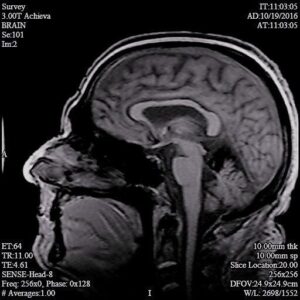

The contours of the cerebrum, cerebellum, and brainstem are outlined with a T2 hypointense signal with blooming on susceptibility weighted sequences, which is compatible with the clinical history of superficial siderosis. A majority of the T2 hypointense signal is present in the superior folia of the cerebellum but also seen coating the surfaces of the brainstem, the cortical surfaces along the Sylvian fissures, and the cortical surfaces of the paramedian sulci of the frontal and occipital lobes. Few subcortical and periventricular T2/FLAIR hyperintensities are present in both cerebral hemispheres.²

If you look at each image, you can see the dark areas where his hemosiderin deposits are. The radiologist will use the same machine and settings, so we should visually compare the new images with these for some positive change.³